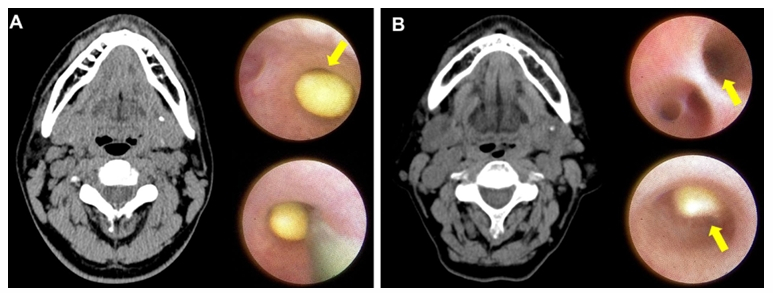

타석은 침을 생산하는 기관인 침샘(타액선)이나 침샘으로부터 입 안쪽으로 연결된 침샘관, 타액선관에 석회 물질, 이물질, 세균 등이 뭉치면서 침의 통로를 막아 생겨난 돌을 가리킨다. 이렇게 생긴 타석이 손으로 만져지지 않는 '고난도 턱밑샘 타석증'을 치료할 때 내시경 시술이 가장 효과적이라는 연구 결과가 나왔다.

턱밑샘 타석증은 침샘에 결석이 생겨 침의 흐름을 방해하고 염증·통증을 유발하는 질환이다. 특히 턱밑샘 깊은 곳이나 혀 근육 아래 위치한 결석은 촉진이 어렵고 제거가 까다로워 치료법 선택이 중요하다.

또 이번 연구에서는 내시경 보조 타석 제거술을 통해서 더 작은 크기의 더 깊은 곳에 있는 실질 내 타석들도 제거할 수 있다는 사실도 재확인했다.